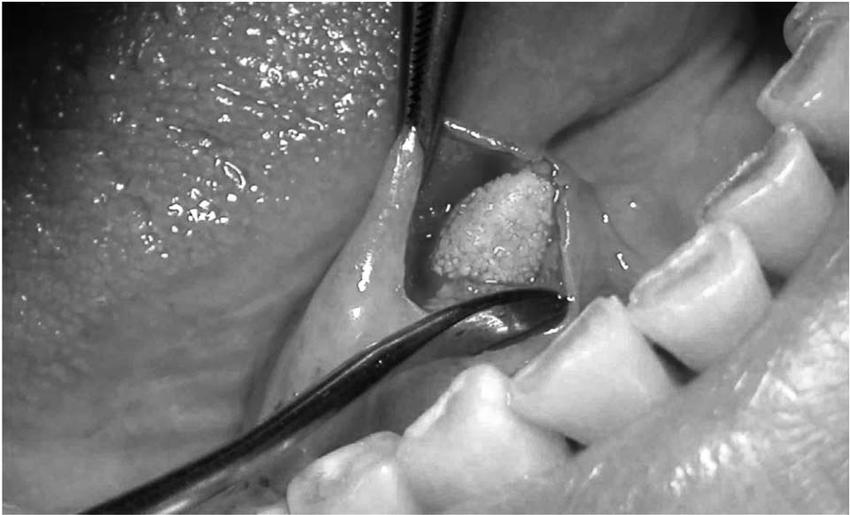

到医院做了超声和CT检查后,发现李女士有个唾液腺结石,约4mm,用手指可以在倒数第二个磨牙里摸到它。医生表示,李女士最近的症状都是因为这个结石导致的。

如果结石大到堵住导管,就需要就诊治疗。医生会借助探针、内窥镜等发现结石,并将其移除;针对大且深的唾液腺结石,可以考虑对结石使用超声波将其粉碎,再取出,甚至有的时候医生需要通过切开唾液腺导管去除石头,将整个腺体摘除。